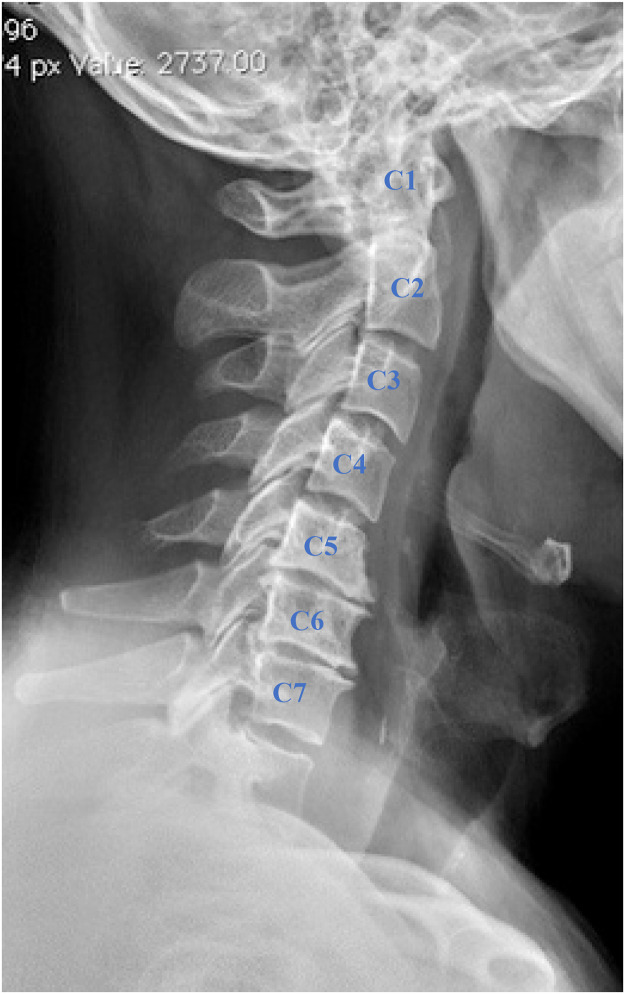

To minimize variability in cervical degeneration, inclusion criteria required all patients to have cervical DDD with similar degrees of degeneration, limited explicitly to mild to moderate degenerative changes (Fig. 2). Severe degeneration, such as multilevel spondylotic myelopathy or advanced kyphotic deformities, was excluded to standardize preoperative spinal balance and degenerative status across cohorts. Spinal balance was maintained by ensuring that all patients had preoperative cervical sagittal vertical axis (SVA) within normal parameters (<40mm), as deviations from normal SVA have been linked to poorer surgical outcomes [11] (Fig. 3). Two fellowship-trained orthopedic spine surgeons assessed these radiographic determinants.

Fig. 2.

Lateral cervical spine x-ray of a patient with mild to moderate cervical degenerative disc disease illustrating disc space narrowing at C5-C6 and C6-C7 levels and the formation of anterior osteophytes.